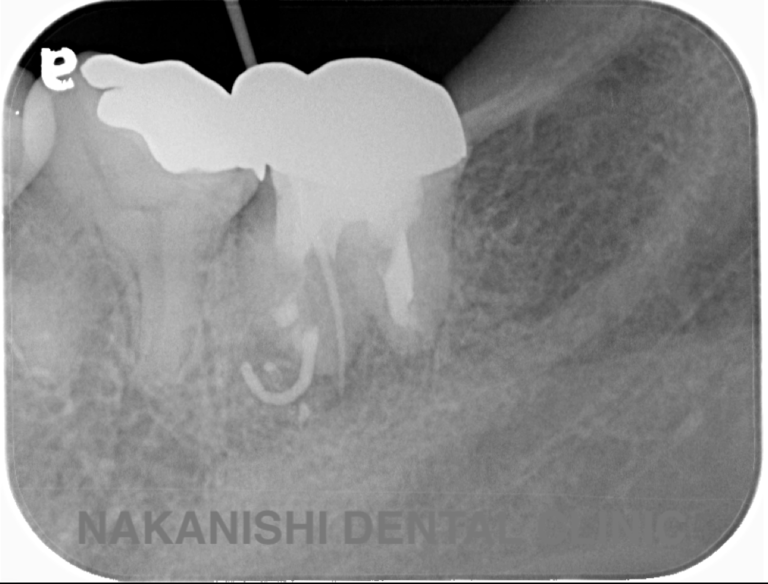

case 1.

治療前

治療後

| 主訴 | 右下歯ぐきの腫れ。 他院で抜歯と言われ、セカンドオピニオン希望でご来院。 |

|---|---|

| 治療期間 | 1か月 |

| 治療費 | 約2万円 |

| 治療内容 | ラバーダム、マイクロスコープ下にて根管治療を施術。歯肉腫脹と疼痛は消失し補綴物を作製し治療終了。治療後のレントゲン写真は2年後のものです。 |

| 治療のリスク | マイクロスコープやCTを使用し、可能な限り精密な根管治療を行っていますが、歯根の形態や病変の大きさ、過去の治療履歴などにより、治癒が得られない場合があります。 また、治療後に再感染や歯根破折が生じることもあり、その場合は再治療や抜歯が必要となることがあります。 治療結果には個人差があり、すべての症例で同様の経過を保証するものではありません。 |